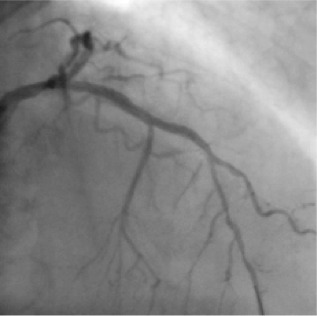

72 year old male with bronchitis and diabetes had severe Breathlessness since 3 days which progressed to Breathlessness on talking short sentences. ECG showed a massive heart attack. 2D ECHO showed that his heart pumping was reduced to only 40%.

Angiography showing badly calcified and diseased left anterior descending artery (lad) with a 100% block.

Based on this IVUS image, a large stent was deployed and the artery was opened and blood flow was restored.

Patient was discharged in 48 hours and resumed his normal job within 7 days. 1 year later, his stress perfusion scan is absolutely normal.

The final result after placing one stent in the lad artery, restoration of flow back to normal and halting the progress of the heart attack